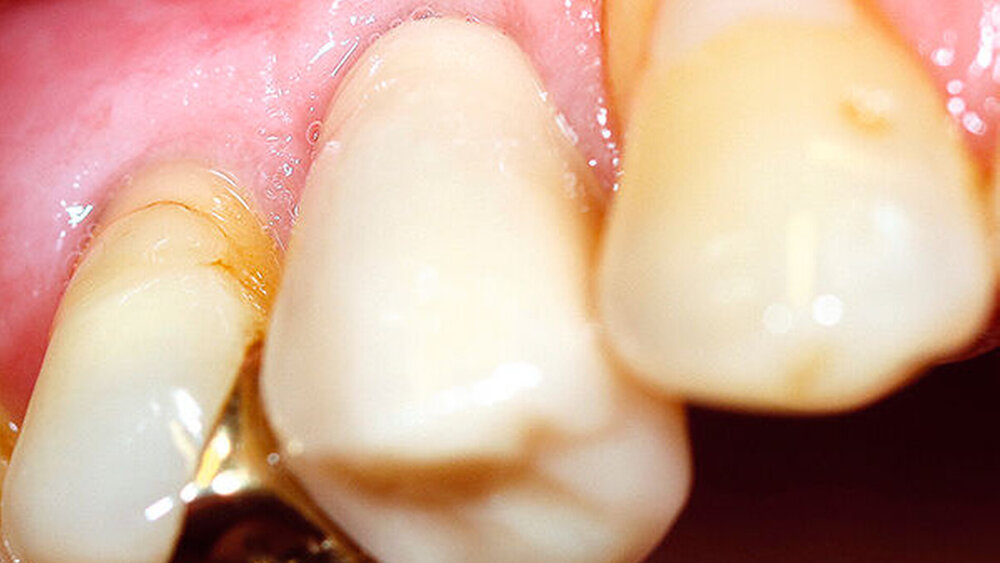

Der folgende klinische Fall dokumentiert die Behandlung eines 61 Jahre alten Patienten, der sich initial mit erheblichen Beschwerden an Zahn 14 vorgestellt hatte. Die radiologische Untersuchung (Abb. 1) ergab eine periapikale Aufhellung sowie eine insuffiziente Wurzelkanalbehandlung. Im Folgenden wurde die Krone entfernt und eine Revision der Wurzelkanalbehandlung durchgeführt. Im Rahmen der Revisionsbehandlung stellte sich eine Längsfraktur im Bereich der vestibulären Wurzel dar. Aufgrund der daraus resultierenden schlechten Prognose einer weitführenden konservierenden Therapie wurde der Zahn atraumatisch entfernt und die Alveole sorgfältig von Granula‧tionsgewebe und einem sich apikal befindenden Zystenbalg befreit (Abb. 2). Das gewonnene Gewebe wurde der histopathologischen Untersuchung zugeführt; dabei ergab sich das Bild einer radikulären Zyste. Aufgrund der latent vorhandenen Inflammation im Bereich der Alveole wurde auf eine sofortige Augmentation mit Knochenersatzmaterial im Sinne einer Ridge Preservation verzichtet. Die Alveole wurde konventionell mit einem Kollagenkegel und einer adaptierenden Naht versorgt. Nach Besprechung mit dem Patienten wurde eine implantatprothetische Versorgung geplant. In der ersten chirurgischen Phase (sechs Wochen nach der Extraktion) erfolgte ein horizontaler Alveolarkammaufbau mittels GBR-Technik unter Lokalanästhesie, um das abgebaute Knochengewebe wiederherzustellen und damit ein entsprechendes Implantatbett zu gestalten. Präoperativ zeigten sich vestibulär in regio 14 sowohl der Knochen als auch das Weichgewebe defizitär (Abb. 3). Im Rahmen der geplanten Augmentation erfolgte die Bildung eines lokalen Mukoperiostlappens in regio 14. Aufgrund der aus den vorhergegangenen operativen Eingriffen resultierenden Narbenzüge im OP-Gebiet wurde auf eine gängige Lappenextension über das Augmentationsgebiet hinaus verzichtet. Nach Lappenbildung konnte der wandige Defekt exploriert und intensiv mit physiologischer Kochsalzlösung gespült werden (Abb. 4). Im Anschluss erfolgten die Vorlage einer neuen nicht resorbierbaren Membran (permamem, botiss biomaterials, Zossen, Deutschland) sowie der Zuschnitt der Membran entsprechend der Größe des abzudeckenden Defekts (Abb. 5). Es folgte die Augmentation des wandigen Knochendefekts mit allogenem Knochenersatzmate‧rial (maxgraft spongiöse Granula, botiss biomaterials), das zuvor mit venösem Eigenblut des Patienten durchmischt worden war (Abb. 6 und 7). Danach wurde das Augmentat mit der vorgelegten nicht resorbierbaren Membran abgedeckt (Abb. 8). Der Wundverschluss erfolgte mittels horizontaler Matratzennaht und Einzelknopfnähten (Resolon 4.0/5.0, Resorba, Nürnberg, Deutschland) (Abb. 9). Die postoperativ angefertigte Halbseiten-Panoramaschichtaufnahme zeigte eine vollständige Augmentation der Defektregion (Abb. 10).